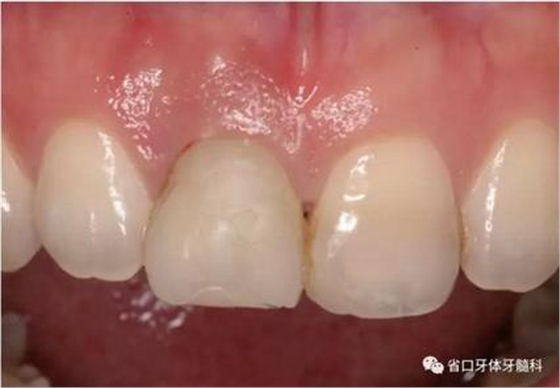

圖1 術(shù)前口內(nèi)照

圖2 術(shù)前口內(nèi)照

圖3 術(shù)前口內(nèi)照

1.?病例簡介 43歲女性患者,主拆:右上前牙松動不適數(shù)日要求修復(fù)。現(xiàn)病史:患者數(shù)年前右上前牙因“齲壞”于外院行根管治療(具體不詳),數(shù)日前牙冠松動不適,現(xiàn)覺影響咀嚼及美觀,遂來我院要求進(jìn)一步診治。否認(rèn)高血壓、心臟病等重大疾病,否認(rèn)結(jié)核、肝炎等傳染病史,否認(rèn)手 術(shù)、輸血史等,未發(fā)現(xiàn)藥物過敏。無吸煙習(xí)慣。臨床檢查:口外觀顏面基 本對稱,皮膚無紅腫破潰,顳下頜關(guān)節(jié)區(qū)無彈響、雜音、壓痛,開口度約 37mm,開口型“↓”,頜下、刻下和頸部未及腫大淋巴結(jié)。中位笑線??趦?nèi)檢查,口腔衛(wèi)生可,色素(+),BOP(-),PD=2mm,上頜右側(cè)中切 牙冠部變色,冠根折斷至齦下3mm,叩不適,松動Ⅱ°~Ⅲ°。牙齦稍紅, 齦緣水平及齦乳頭高度可,屬于中厚齦生物型,附著齦寬度約5mm,唇系帶附著可。上頜右側(cè)中切牙缺牙間隙與對側(cè)同名牙一致,約>7mm,修復(fù)空 間良好。與對頜牙覆合覆蓋正常。MCT檢查示上頜右側(cè)中切牙冠根折斷至骨 下,根管內(nèi)見充填物,根充不全,根尖見陰影,大小約3mm×3mm。牙槽窩根方可用骨量可,唇側(cè)骨壁完整,冠方骨壁厚度約1mm。